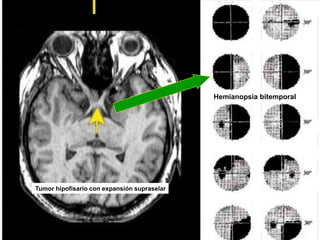

Traumatismo con fractura de orbita izquierda

Tumor hipofisario con expansión supraselar

Hemianopsia bitemporal

drpabloarias@hotmail.com Fisiología de laVisión 46 Traumatismo con fractura de orbita izquierda Tumor hipofisario con expansión supraselar Hemianopsia bitemporal